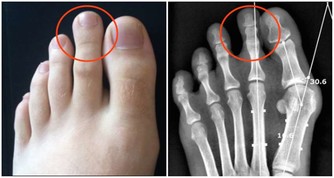

內庭穴

滎穴可以說是熱症、上火的剋星。如果有口臭、便秘、咽喉腫痛、牙痛、腹脹、吐酸水等不適時,可以多按內庭穴。

嘴上長泡,暗藏6種致命疾病,做對5件事清火排毒!

按摩手法:內庭穴是在第二足趾和第三足趾之間的縫隙交叉處,每天早晚用大拇指點揉100次即可。